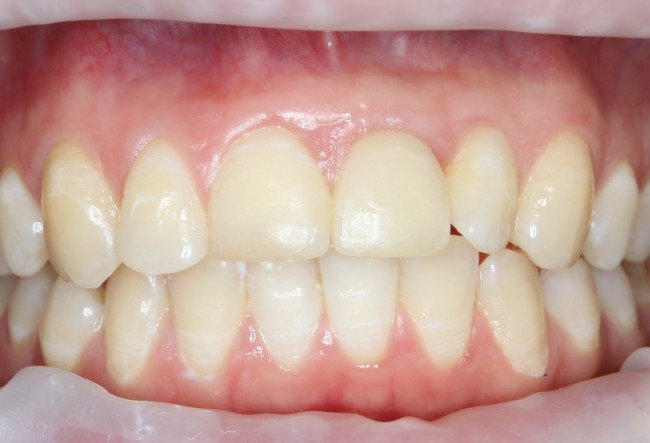

Делаем анестезию, разрез, скелетируем костную ткань:

На фотографиях хорошо видны оставшиеся после удаления объемы костной ткани. Давайте рассмотрим плюсы и минусы текущей клинической ситуации, применительно к нашему плану:

Фактически, альвеолярный гребень атрофировался по толщине примерно наполовину — это минус.

Зато с высотой все в порядке — это плюс

Немедленная нагрузка на имплантат невозможна — это минус. Почему? (см. Факторы…)

Достаточный объем кератинизированной десны, который даст нам возможность герметично запечатать послеоперационную рану — это, несомненно, тоже плюс. (вспомним факторы успеха остеопластической операции, часть III)

Ну и, оставшиеся объемы костной ткани позволят нам установить и правильно позиционировать имплантат — это главный плюс. А значит, мы обойдемся одной операцией вместо двух.

Итак, позиционируем имплантат. Для начала, с помощью пина:

Лунка готова, устанавливаем имплантат:

Это Nobel Replace CC 3.5×13 mm. Оптимальный размер импланта для работы в этом клиническом случае.

Продолжим нашу работу. Имплантат установлен:

Работа закончена? Отнюдь, нет. Теперь наша задача — восстановить утраченные объемы костной ткани вокруг импланта. Ибо, как вы видите на фото, его вестибулярная поверхность, практически, просвечивает. И, если ничего не делать, дальше будет только хуже.